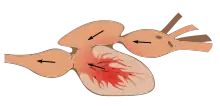

The human circulatory system (simplified). Red indicates oxygenated blood carried in arteries. Blue indicates deoxygenated blood carried in veins. Capillaries join the arteries and veins. | |